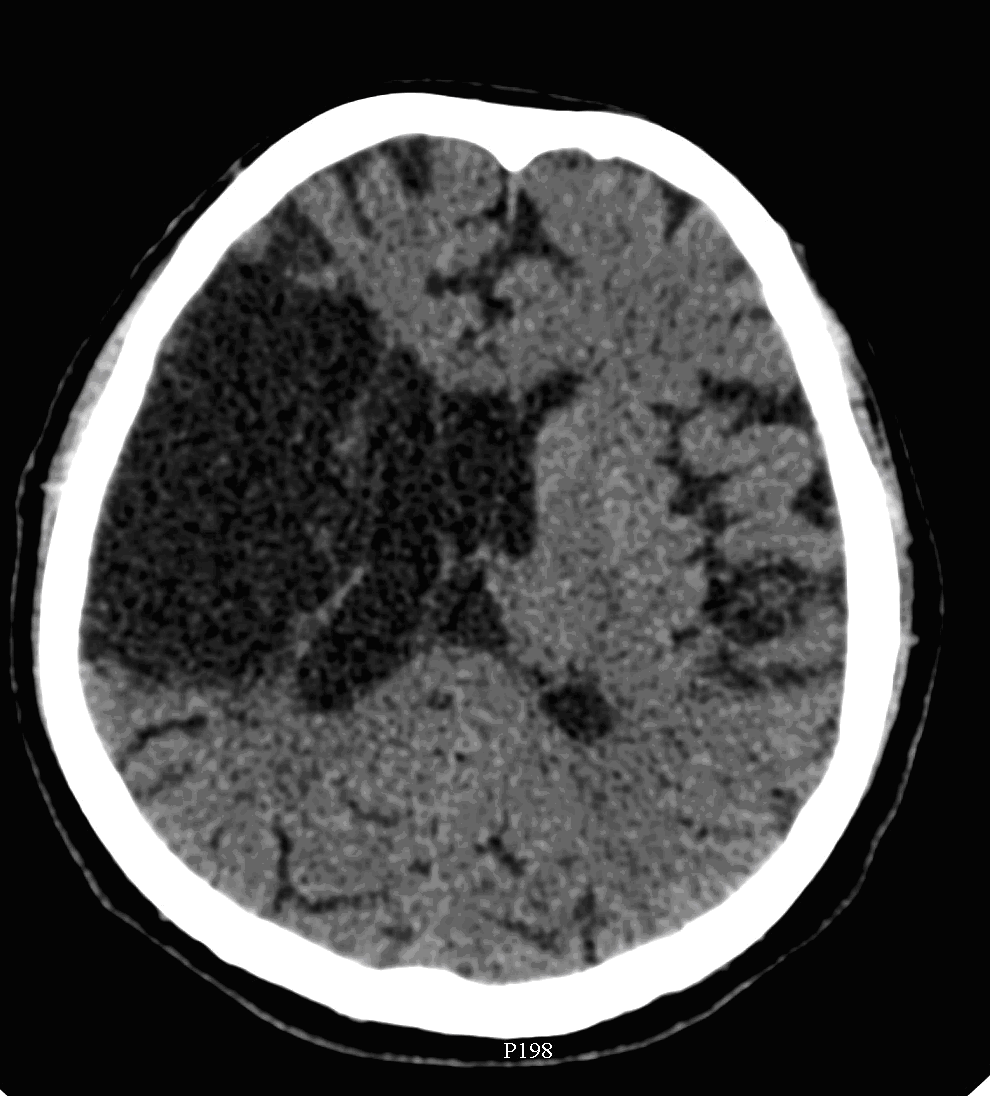

In acute phase (12-24 hours after the occlusion of the middle cerebral artery) on CT hypodense basal ganglia, the loss of cortical white-grey matter differentiation and sulcal effacement are the characteristic imaging findings.

After 1-3 days the “mass-effect” of the infarct increases. It is more apparent in case of large territorial infarcts, the sulcal effacement completes, the loss of cortical white matter and grey matter differentiation is more pronounced (especially in the white matter) due to the increased hypodensity. Hemorrhagic transformation in the grey matter (cortex, basal ganglia) can also occur at this stage. It is worth to note, that for hemorrhagic transformation one should not always blame thrombolytic therapy; it rather occurs spontaneously in a great majority of the cases.

After 4-7 days the edema and the “mass-effect” persist, there is a marked hypodensity and even contrast enhanced CT can detect enhancement at the leptomeningeal border of the infarct zone.